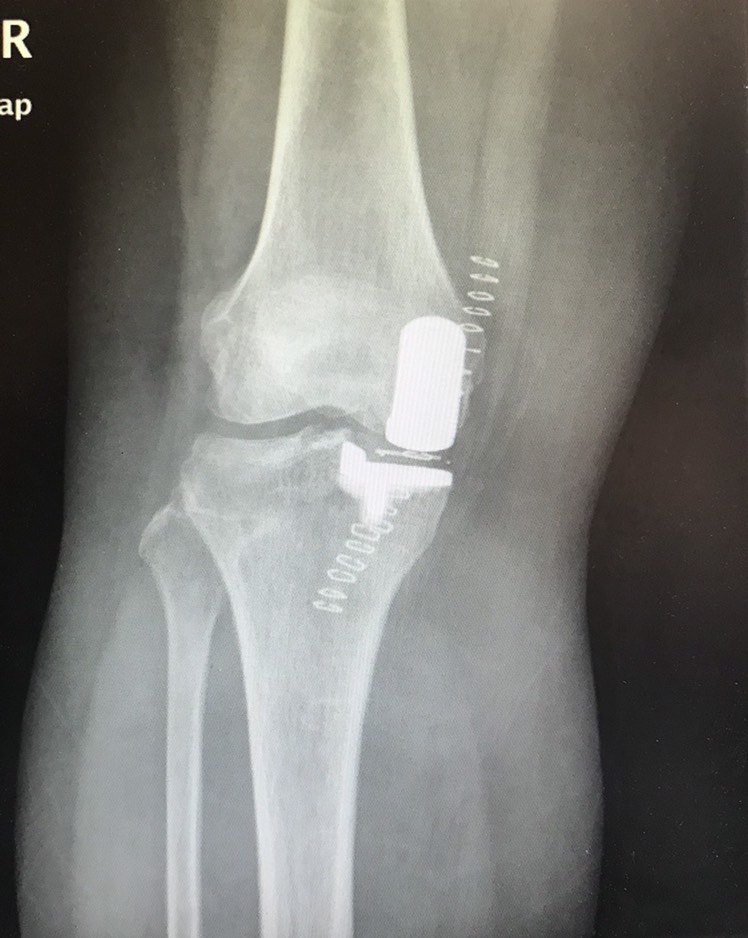

杨浦医院使用微创手术患者换 半个 小半个 膝关节两天内即可出院 假体 手术 患者 新浪新闻

Apr 04, 15 · 脚踝上长骨刺能动手术吗?拍片了,说不能动手术? 3回答 做阑尾手术半麻穿骨刺 现在后腰针眼很疼连着整个后背 有啥办法吗 3回答 我是骨关节炎腿膝盖有骨刺能吃仙灵骨葆吗 3回答 怎样区别骨刺与鸡眼 2回答 骨刺清理手术后近两个月可以下地活动吗 2回答Nov 09, 09 · 什么是膝关节微创手术 发病时间:不清楚 说是我的左膝关节骨折,半月板塌陷,现在已经9天了 补充问题1: ( ) (必填,150个汉字以内)谢谢你,医生,那做了微创手术以后一般需要多久能恢复,需要半身麻醉吗? 还有手术以后需要石膏绑吗,谢谢Nov 11, 14 · 膝关节骨刺微创手术 来源:网络 时间: 发布者:xiaobai 现在技术发达了,不管身体出现什么状况,都会有相应的医学技术来缓解,下面小编就来带大家了解一下膝关节骨刺微创手术。

膝盖长骨刺行走困难 专业医院微创拔刺解病痛 每日头条

膝关节炎如何治疗 微创关节科 北京中医药大学第三附属医院